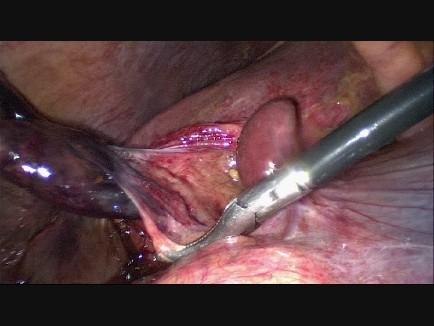

We describe the case of an 89-year-old Caucasian woman who presented with clinical symptoms suggestive of acute cholecystitis to our hospital. Radiological imaging confirmed our clinical diagnosis. At first we considered percutaneous gallbladder drainage because of her age and comorbidity, but instead performed laparoscopic cholecystectomy because of rapid clinical deterioration. During laparoscopy a necrotic gallbladder due to torsion of the gallbladder around the cystic duct was found.

我们描述了一名89岁白种女性的病例,她因出现提示急性胆囊炎的临床症状前来我院就诊。影像学检查证实了我们的临床诊断。起初,由于她的年龄和合并症,我们考虑进行经皮胆囊引流,但由于临床症状迅速恶化,我们改为进行腹腔镜胆囊切除术。在腹腔镜检查中,发现胆囊因围绕胆囊管扭转而坏死。